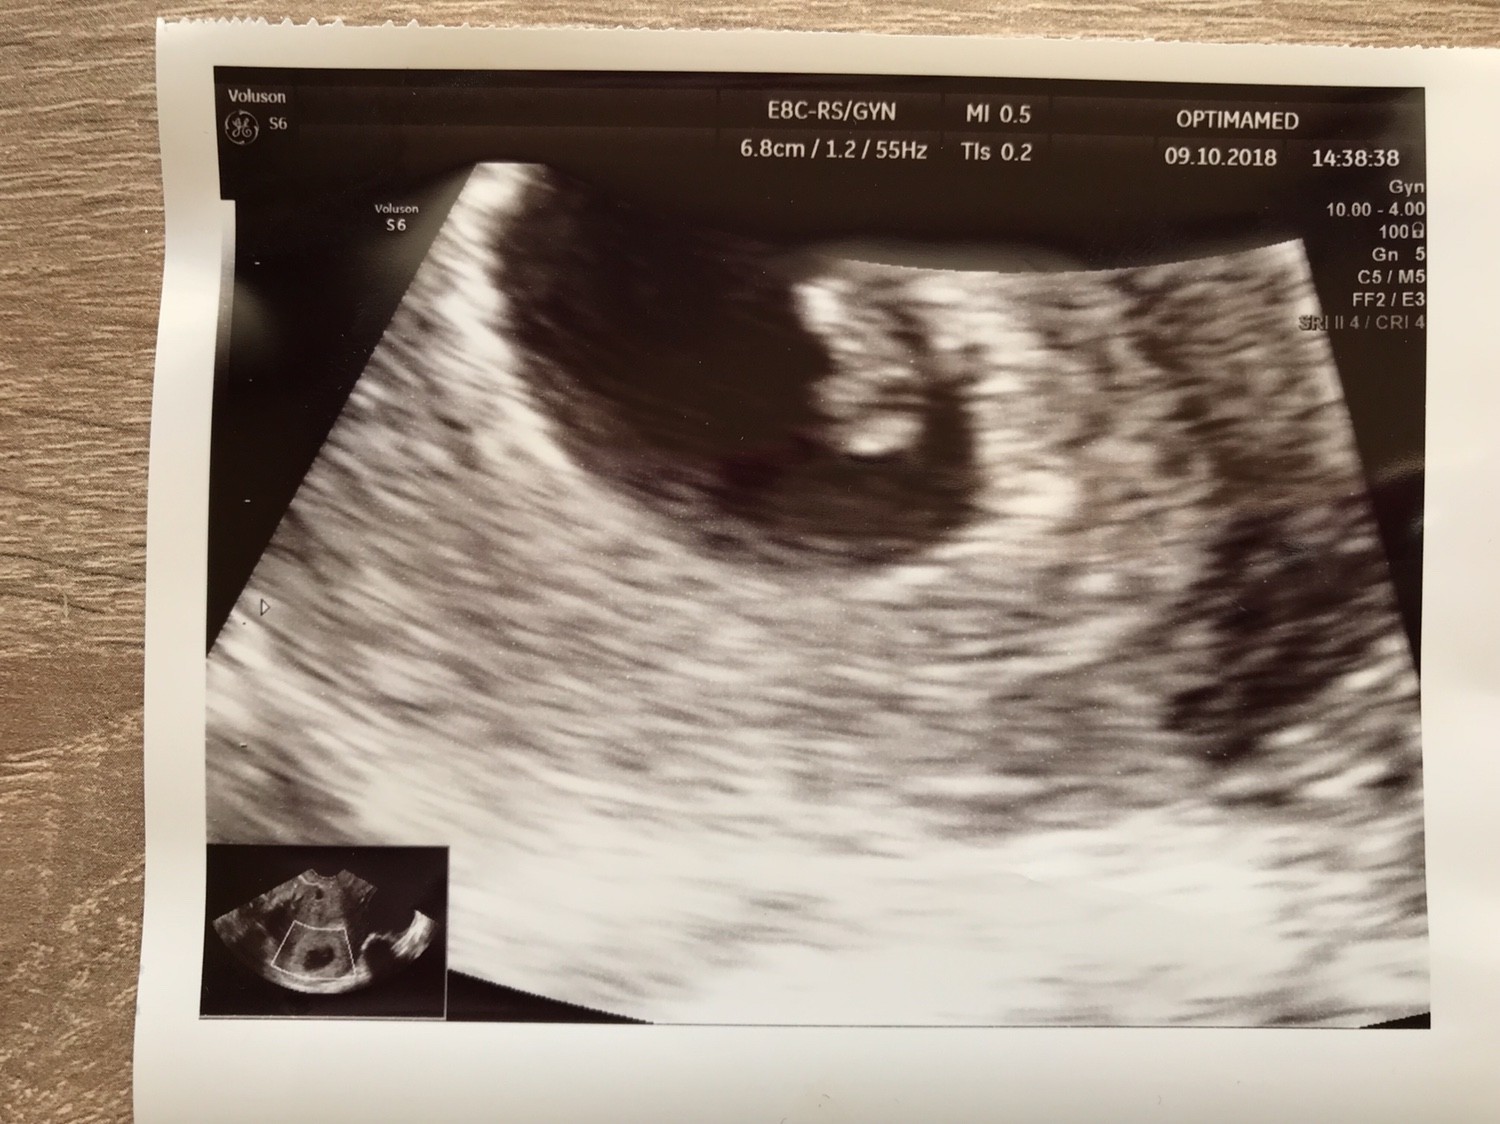

To i ja się pochwale moją małą fasolką [emoji7] Dzisiaj 7tc, na usg 6+4, widziałam bijące serduszko, ale jeszcze nie słyszałam [emoji20] 0,57cm cudu i największego szczęścia [emoji7]

Załączniki

• IMG_3605.JPG

IMG_3605.JPG

298,1 KB · Wyświetleń: 532